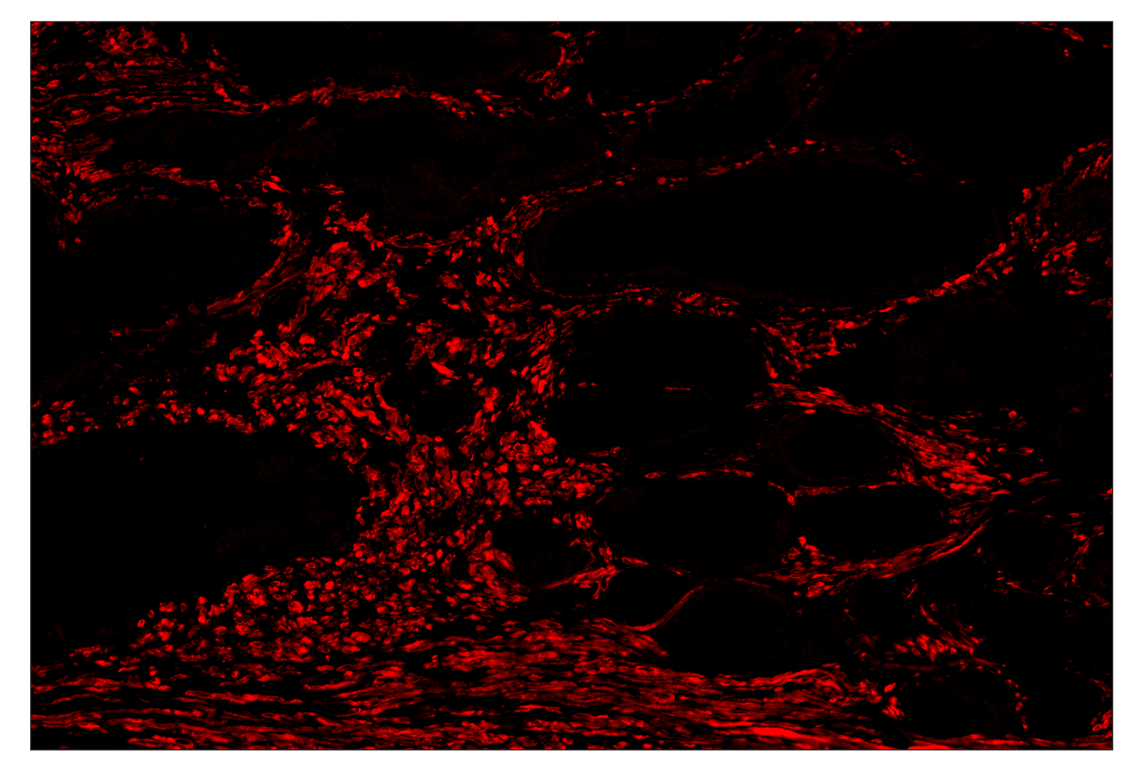

SignalStar™ multiplex immunohistochemical analysis of paraffin-embedded human prostate adenocarcinoma using OX40L (D6K7R) & CO-0087-647 SignalStar™ Oligo-Antibody Pair #73292 (red). All fluorophores have been assigned a pseudocolor, as indicated. Staining was performed on the BOND RX autostainer by Leica Biosystems.

Immunohistochemistry Image 4: OX40L (D6K7R) & CO-0087-488 SignalStar<sup>™</sup> Oligo-Antibody Pair